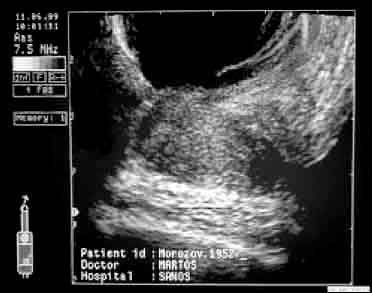

| ТРУЗИ простаты больного М., 1952 г.р. до лечения. Поперечное (а) и продольное (б) сканирование. Снижение эхогенности ткани в области верхушки железы и в виде радиальных полос от вентральной поверхности к центру железы - результат пальцевого массажа. Определяется периуретральный и паравезикальный отек. | |